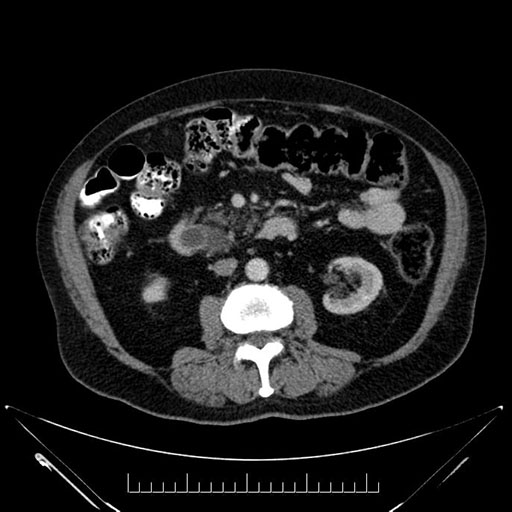

Whipple (pancreaticoduodenectomy) [case 7]

Imaging Analysis

Look through the patient's CT scan to identify any areas of concern for the necessary procedure.

Based on your CT findings, which issue(s) would give reason for "planned slowing down moment(s)" in this case?

Considering a standard Whipple procedure, what step(s) of the operation would you do differently in this case?